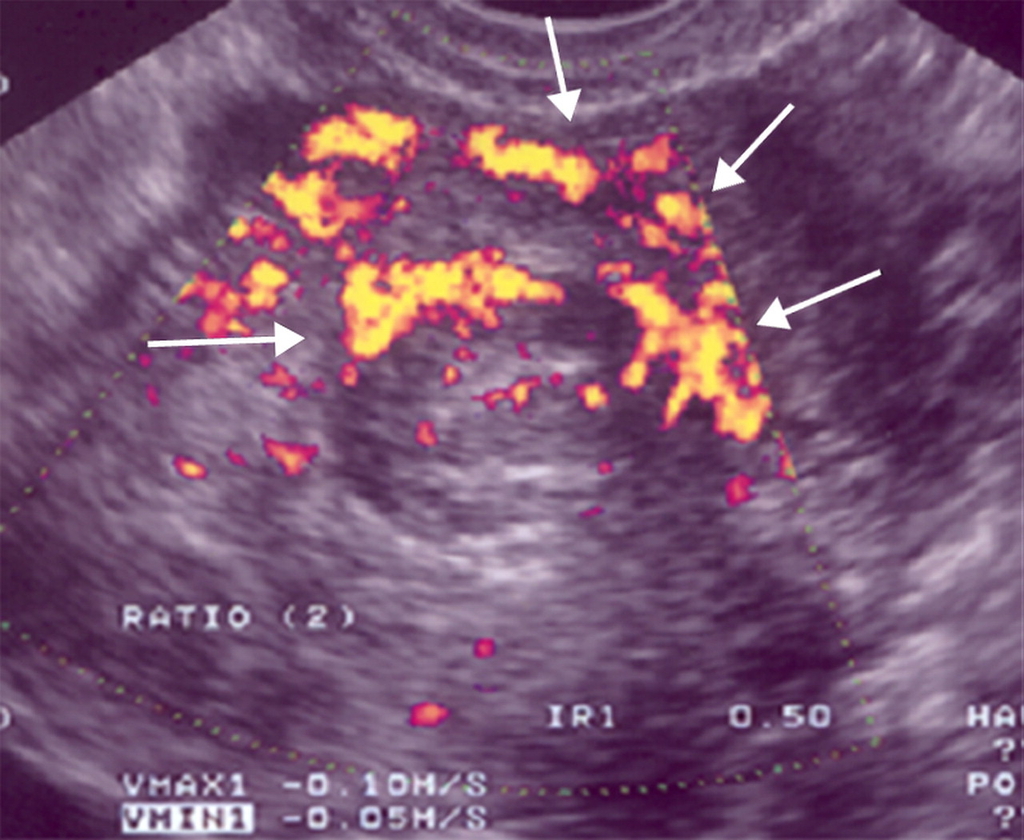

Miomi maternice